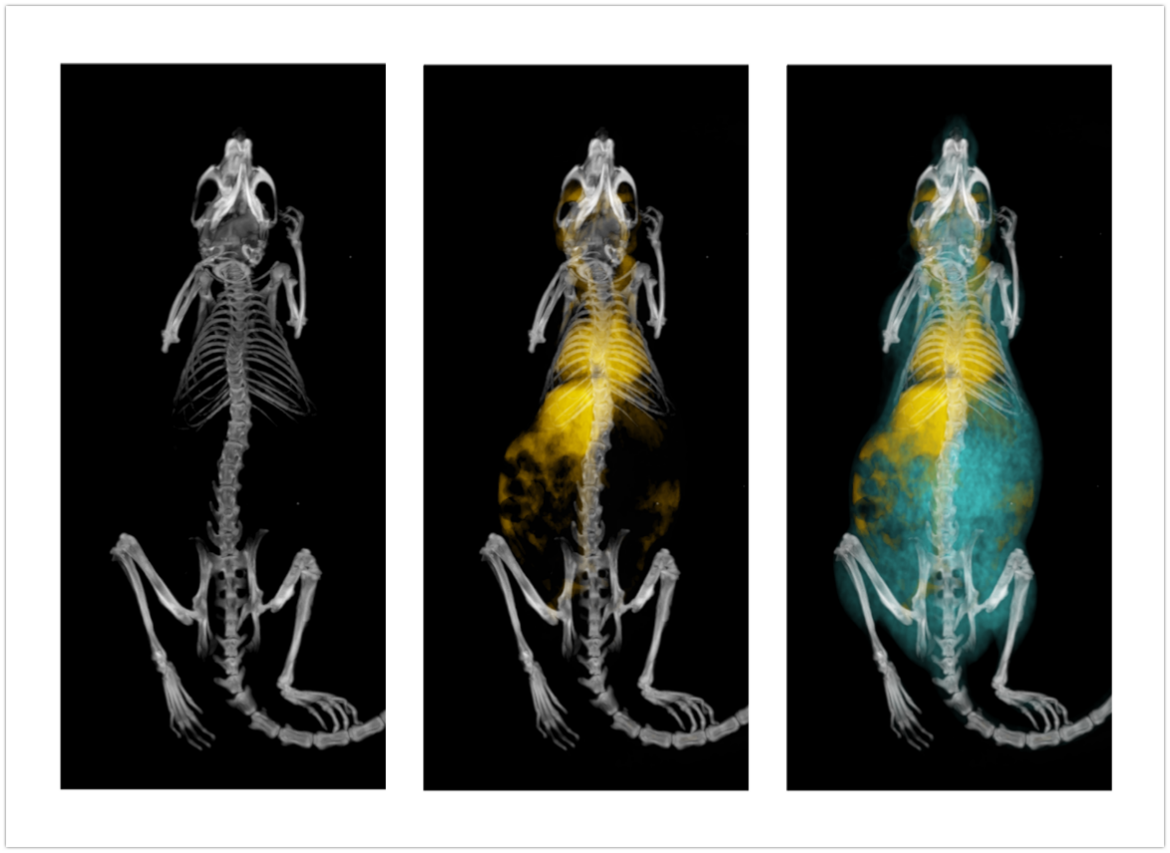

随着临床前研究向着活体成像、高分辨成像、多模成像等应用发展,传统的显微CT技术已无法满足生命科学领域的研究需求。近年来,基于光子计数探测器的能谱CT已成为当前CT新技术的重要发展方向,高分辨X射线能谱CT成像技术正在快速发展。在中科院装备研制等项目的支持下,项目团队研发出国际首台小动物活体能谱显微CT设备,通过以微米级分辨及多能谱图像再现动物体内的各器官组织的精细结构,实现动物实验从离体到活体、从黑白到彩色的进步,为生物医学研究提供更为先进的实验手段和科学仪器。

小动物活体能谱显微CT已经为国内科研院所、高校和医院完成了一批高质量动物实验,未来能够为口腔疾病研究、骨研究、肿瘤研究、心血管疾病研究、生物材料研究和开发、新药开发等多个领域提供先进的研究工具。

鼠全身成像

鼠钆剂造影成像